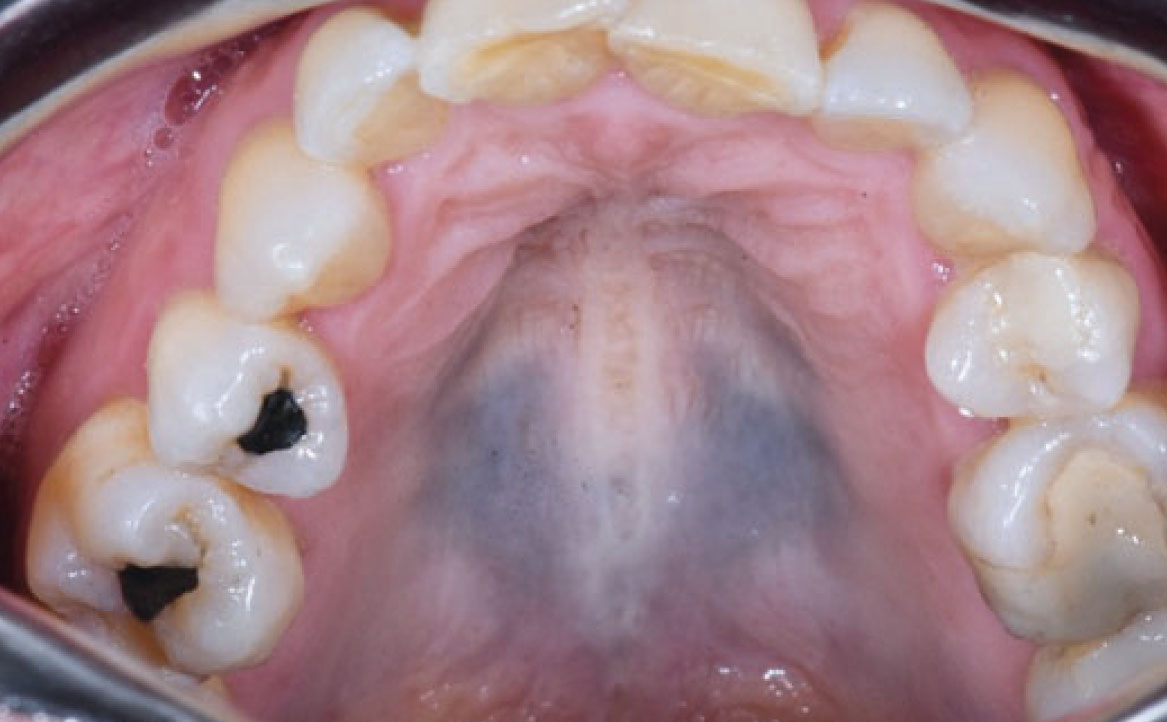

Le pigmentazioni orali causate dai farmaci possono essere classificate in due categorie principali: endogene ed esogene. Le pigmentazioni endogene sono causate dalla deposizione di pigmenti endogeni, come l’emoglobinuria o l’emocromatosi, mentre le pigmentazioni esogene sono il risultato della deposizione di pigmenti esogeni contenuti nei farmaci o nei loro metaboliti (21). Diversi farmaci sono stati associati alla comparsa di pigmentazioni della mucosa orale. Tra questi vi sono alcuni antibiotici come la tetraciclina e la minociclina, che possono causare una pigmentazione bluastra o grigiastra della mucosa. Altri esempi includono farmaci antimalarici come la clorochina e l’idrossiclorochina, che possono causare una pigmentazione marrone o grigiastra, e farmaci antiretrovirali come la zidovudina, che può causare una pigmentazione nera della mucosa (fig. 8) Alcuni farmaci possono indurre la melanogenesi, come contraccettivi orali, clorpromazina, farmaci citotossici come ciclofosfamide e busulfan (25). Pigmentazioni della mucosa orale possono essere indotte da molti altri farmaci, tra cui anche chemioterapici (imatinib, bleomicina, clofazimina, doxorubicina, busulfan, ciclofosfamide). Imatinib, in particolare, utilizzato nel trattamento di alcuni tipi di cancro, tra cui la leucemia mieloide cronica (LMC), è un inibitore della tirosin-chinasi che inibisce la tirosin-chinasi BCR-ABL mutata della LMC. Inoltre, l’imatinib blocca il legame dei ligandi ai recettori c-kit sui melanociti, riducendo l’attività dei melanociti e portando a ipopigmentazione cutanea, ma nella recente letteratura è stato notato che i pazienti in terapia con imatinib sviluppano iperpigmentazione diffusa nel palato duro (26). La diagnosi di pigmentazione correlata all’imatinib dipende da una storia clinica accurata e dalle caratteristiche cliniche specifiche. Le lesioni iperpigmentate sono benigne e non richiedono trattamento (fig. 9).